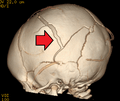

3D CT reconstruction showing a skull fracture in an infant